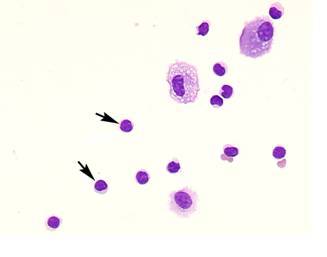

Comparison of lymphocyte morphology between sarcoidosis and HP. Sarcoid-lymphocytes were generally small in size and appeared mature and well differentiated in morphology (Figure 4). They had a round nucleus and the cytoplasm was fairly thin. In contrast, HP lymphocytes had fairly abundant cytoplasm and occasionally developed an elongated cytoplasmic process resembling a hand-mirror in shape. A number of lymphocytes looked like plasma cell, having large basophilic cytoplasm and nucleus with wheel-like appearance. In others, the nuclear membrane was highly convoluted like cerebelli-form or clover-shape. Nucleus often contained a large nucleolus. Sarcoidosis patients consistently showed a different morphology compared with HP patients. Other inflammatory cells, particularly eosinophils and mast cells were also frequently seen in BALF of HP patients (Figure 5).

Figure 4

Morphology of sarcoid lymphocytes. The sarcoid lymphocytes displayed mature, small shape dominant, and also regular size cells. They had round-shape nuclei and scanty cytoplasm. (Giemsa stain x original magnification x 200).

Morphology of hypersensitivity pneumonitis (HP) lymphocytes. HP lymphocytes morphology and diameter varied considerably. The cell morphology was consistent with activated-type lymphocyte. They presented cytoplasmic formations like hand-mirror cells which had cytoplasmic tail (A, arrows), or plasmacytoid cells which had light cytoplasmic regions adjacent to nuclei (B, arrow). They also had irregularities in the contours of the nuclear membranes such as cerebelli-form (B and C, arrowheads), glove mitt-like or clover-shaped. Other inflammatory cells, particularly eosinophils and mast cells (C, arrow) were also frequently seen in BALF of HP patients. (Giemsa stain; original magnification x400).